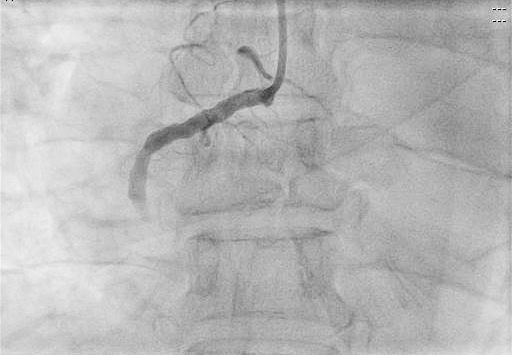

患者進入導管室后,憋喘明顯,血壓、氧飽和度低,需面罩吸氧、大劑量去甲腎上腺素維持血壓。朱宗濤主任建議應使用強支撐指引導管,先用軟導絲輕柔操作,結合血管內超聲(IVUS),嘗試尋找血管真腔。術中選擇6F SAL指引導管行冠狀動脈造影提示右冠中段閉塞,先后嘗試Anyreach、Sion工作導絲未能通過閉塞病變,然后在Finecross微導管輔助下,換用Gaia1硬導絲通過閉塞處成功送至右冠遠端,行血管內超聲(IVUS)檢查顯示血管支架遠段局部夾層、血腫,導絲全程位于血管真腔,在IVUS精確定位下,成功開通血管并植入支架2枚。術后,經CCU醫護人員的精心治療,已于10月10日康復出院。